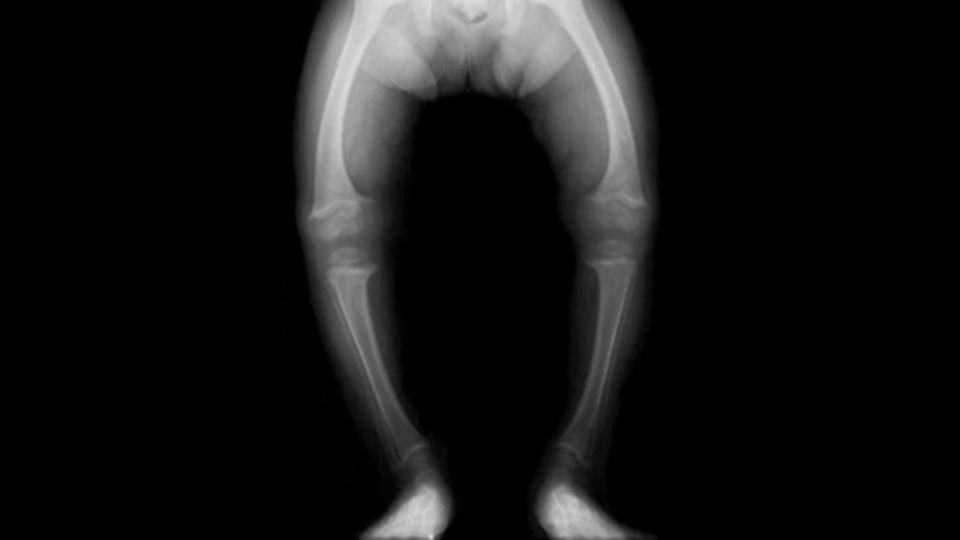

Raşitizm; kemik gelişimini sağlayıcı ve destekleyici kalsiyum ve fosfor gibi vitaminlerin kemiklerde yeterli düzeyde bulunamaması sonucu ortaya çıkan hastalıktır. Genellikle çocuklarda görülen bu rahatsızlık, her yaşta da karşımıza çıkabilmektedir. Bu hastalığı olan kişilerde; kemiklerin şekillenmesi ve gelişmesi sağlıklı olanlara göre daha farklı, düzensiz olmaktadır. Ortaya çıkmasındaki en büyük neden ise; D vitamini eksikliğindendir.

• Bacak eğriliklerinde meydana gelen şekil bozuklukları,